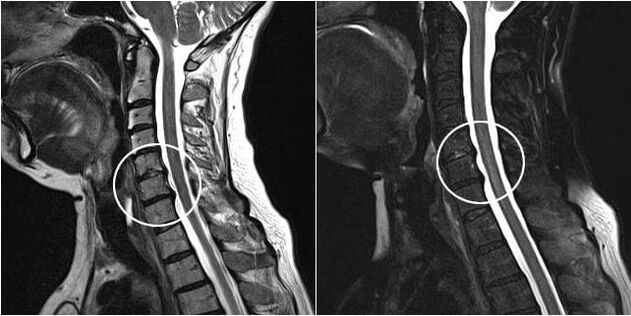

As the intervertebral discs and vertebrae deform, the patient's condition worsens.The course of osteochondrosis is complicated by neurogenic symptoms caused by compression by osteophytes or hernial protrusion of the vertebral roots and vertebral artery.Headaches, dizziness, changes in blood pressure appear, and visual and hearing acuity decreases.

Indications for surgical intervention include the ineffectiveness of conservative treatment, as well as complications of cervical osteochondrosis, for example, discogenic myelopathy, vertebral artery syndrome and radicular syndrome.To decompress the spinal cord, blood vessels and spinal roots, the following operations are performed:

During the surgical procedure, bone fragments and ligaments can be excised and the intervertebral discs can be completely or partially removed.For small hernial protrusions, laser vaporization of the disc nucleus is often performed.

After excision of spinal structures, stabilization of spinal motion segments is often necessary by spinal fusion or by placement of bone and skin autografts.